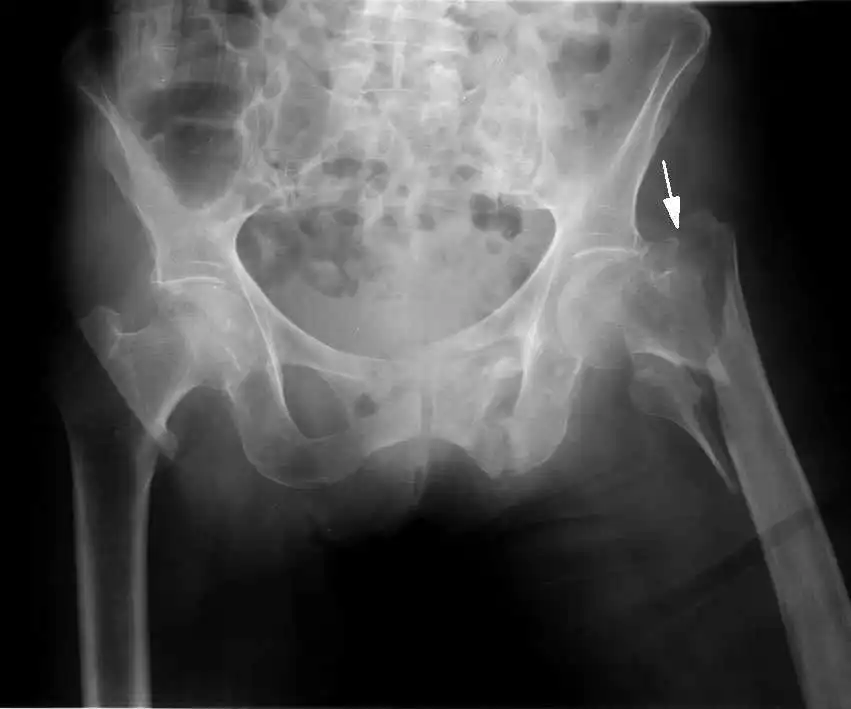

A new study just published in the New England Journal of Medicine of over 31,000 people found that those taking the highest levels of Vitamin D (over 800IU which by many standards is not high at all) had a 30% reduction in him and 14% reduction in non-vertebral fractures. There was no significant reduction in people taking less than 800IU per day.

Bischoff-Ferrari and colleagues found that, in an intention-to-treat

analysis, there was a nonsignificant 10% reduction in the risk of hip

fracture and a significant (at P=0.03) 7% reduction in the risk of

nonvertebral fracture.

On the other hand, when they took into account actual vitamin D intake,

they found a 30% reduction in the risk of hip fracture but only for

those in the highest quartile of intake – 792 to 2,000 IU a day.

The relative risk in that group, compared with controls, was 0.70, with

a 95% confidence interval from 0.58 to 0.86, and was significant at P<0.001.

They also found a 14% reduction in the risk of any nonvertebral

fracture, but again only in the highest quartile. The relative risk was

0.86, with a 95% confidence interval from 0.66 to 0.96, and was

significant at P=0.007.